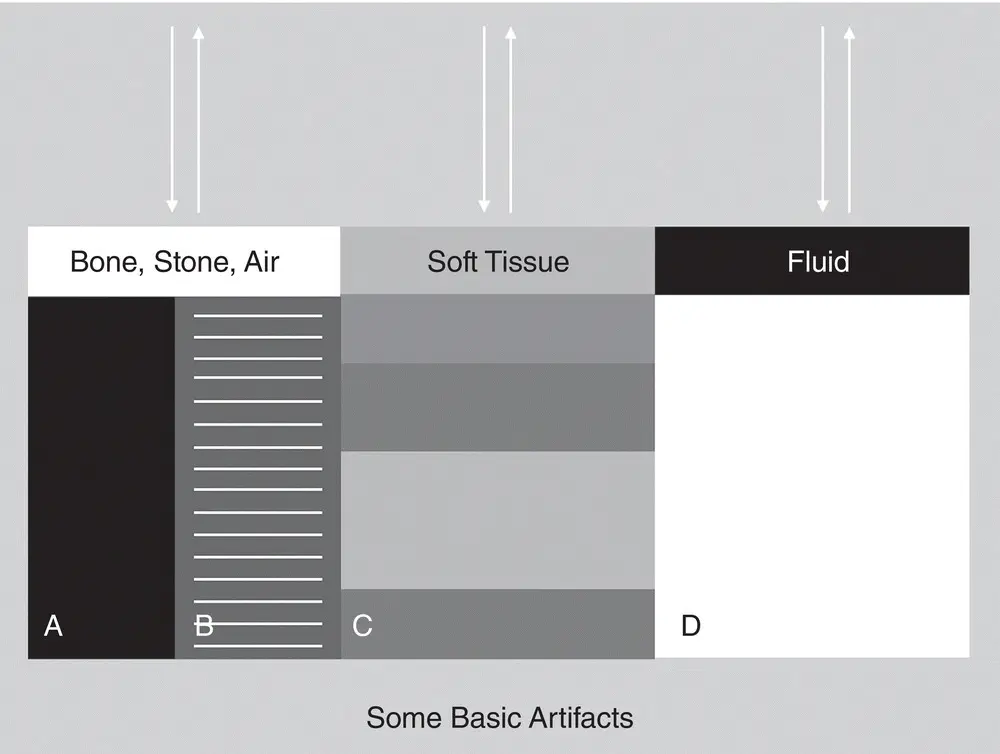

Figure 1.2. The figure shows the ultrasound differences in B‐mode gray scale of various tissues, with bone, stone and air being most reflective of the ultrasound beam and thus portrayed as white along its surface, to soft tissues being shades of gray, to fluid which is black. Ultrasound terminology corresponds to these gray‐scale colors as hyperechoic, degrees of echogenicity (hypoechoic), and anechoic. Study this chart to get the visual of what these gray‐scale terms mean. Courtesy of Dr Gregory Lisciandro, Hill Country Veterinary Specialists and FASTVet.com, Spicewood, TX.

Figure 1.5. Ultrasound and different tissues and elements. Schematic that ties into the previous images showing various elements and the general behavior of ultrasound and its associated artifacts. The arrows represent the ultrasound beam being transmitted and returned to the transducer (probe). In (A) and (B), bone, stone, and air reflect because ultrasound (its echoes) does not transmit through them. As a result, they create shadowing of the beam, resulting in (A) “clean shadowing” (anechoic or black past the surface of the structure or element) or (B) “dirty shadowing,” including air reverberation called A‐lines (hyperechoic horizontal bars past the air). Soft tissues will absorb the ultrasound in different degrees depending on the soft tissue, thus (C) shows different degrees of echogenicity. Lastly, fluid will not absorb much of the ultrasound (echoes pass through the fluid), resulting in (D) acoustic enhancement through the far‐field beyond the distal boundary of fluid, making tissues more hyperechoic (brighter) than their adjacent counterparts outside the fluid‐related beam. Courtesy of Dr Gregory Lisciandro, Hill Country Veterinary Specialists and FASTVet.com, Spicewood, TX.